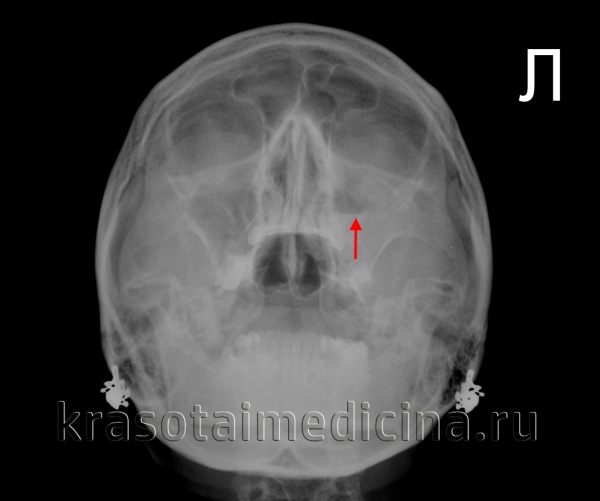

Діагноз виставляється на підставі скарг пацієнта, даних зовнішнього огляду (визначається рефлекторне розширення шкірних судин подглазничной області), огляду слизової носової порожнини (запалення, набряк, гнійні виділення з отвору пазухи). На рентгенограмі гайморової пазухи виявляється затемнення. При недостатній інформативності інших методів дослідження виконується пункція гайморової пазухи.

Рентгенограма придаткових пазух носа. Рівень «рідина-газ» у лівої в/щелепної пазусі